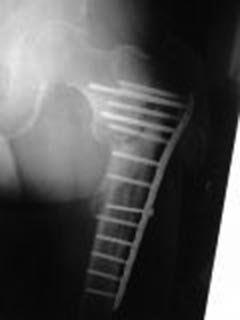

[Ortho] Ложный сустав вертельной области, варусная деформация

Мужчина 63 года, травма в феврале 2013 г. - перелом в/3 левой бедренной

кости. В ЦРБ остеосинтез пластиной LCP.

17.06.2014 г. пластина удалена, стал отмечать боли, патологическую

подвижность в бедре, укорочение левой нижней конечности на 4 см.

04.02.2015 г. в одном из учреждении г. Москвы произведена резекция

ложного сустава, остеосинтез пластиной с пластикой Коллапаном.

На сегодняшний момент беспокоят боли и патологическая подвижность в

области верхней трети левого бедра, укорочение конечности на 4 см,

передвигается при помощи костылей с нагрузкой на оперированную конечность.

Рентгенограммы от 21.04.2015 г. и 16.08.2015 г.

В отделении планируется: удаление пластины, остеотомия, восстановление

ШДУ, фиксация стержнем.

Вопрос: возможно ли выполнить операцию одномоментно или необходимо

аппаратное удлинение бедра?